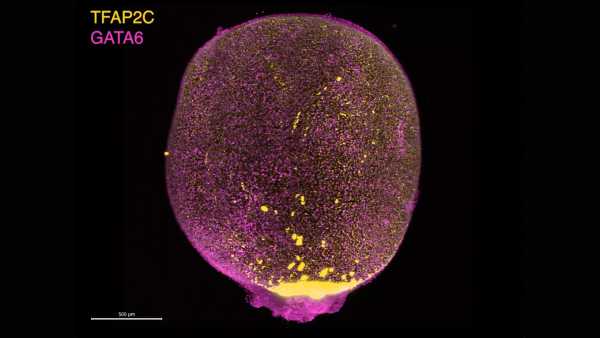

Згідно із заявою, цей експеримент зрештою призвів до отримання 82 яйцеклітин, які потім були запліднені сперматозоїдами за допомогою екстракорпорального запліднення (ЕКЗ). Однак етап запліднення ще не є безпомилковим — лише близько 9% досягли стадії «бластоцисти». На цьому етапі яйцеклітина ділиться, утворюючи порожнисту сферу клітин, яку можна ввести в матку за допомогою ЕКЗ.

«Скромний» темп розвитку бластоцист, ймовірно, пов'язаний з двома факторами, пишуть автори дослідження у своїй статті. По-перше, хромосомні аномалії, ймовірно, перешкоджали подальшому поділу запліднених яйцеклітин. А по-друге, гени, перенесені з клітин шкіри, ймовірно, не були успішно перепрограмовані для підтримки ембріонального розвитку. Іншими словами, в деякому сенсі гени все ще активувалися так, ніби вони знаходилися в клітинах шкіри, а не в клітинах, що формуються на ранніх стадіях розвитку.

Жодна з яйцеклітин, що досягли стадії бластоцисти, не була вирощена далі, і оскільки вони також мали хромосомні аномалії, малоймовірно, що вони були б придатними для використання в ЕКЗ, зазначили дослідники. Ці аномалії включали занадто багато або занадто мало хромосом, хоча в середньому їх було 46. Деякі яйцеклітини також несли кілька копій однієї й тієї ж хромосоми або взагалі не мали певних хромосом.